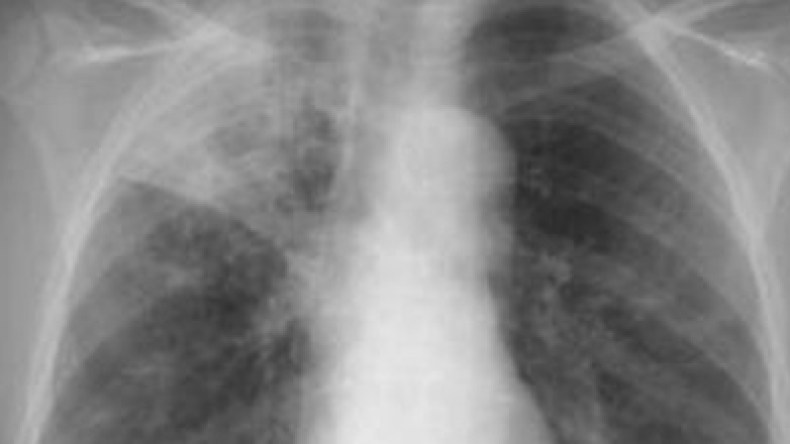

ارتفعت حصيلة الطاعون الأبيض الى73 ضحية منذ استفحال داء السيليكوز وسط الشبان الممتهنين لصقل الحجارة بدائرة تكوت ولاية باتنة، حيث سجلت خلال الشهر الفائت وفاة ضحيتين أخريين، ويتعلق الأمر بغمري إبراهيم وغقالي كمال.

1هذا الداء ليس جرثومي بل نتيجة تكدس غبار الحجارة في الرئتين ويسمى علميا silicose و هو إستنشاق مادة سيليس silice عند قطع الحجارة (هذا للتوضيح فقط)